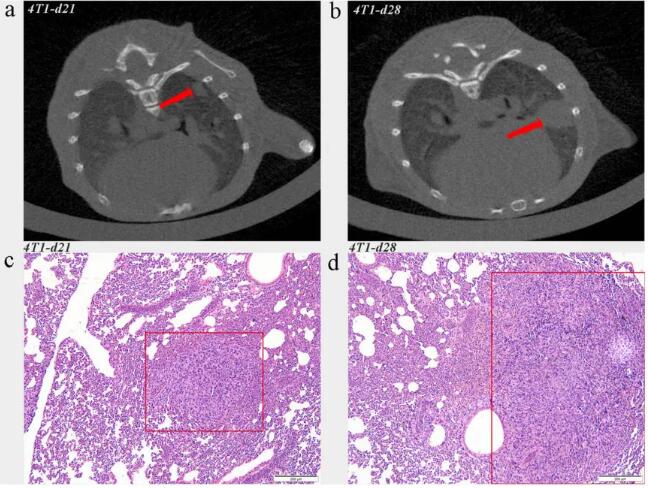

在本研究中,將 4T1 乳腺癌細(xì)胞接種到 Balb/c 小鼠耦合的腹部乳腺中,建立腫瘤模型。把小鼠分為對照組和 4T1 實(shí)驗(yàn)組,然后就要用到 Micro-CT(Hiscan XM,Suzhou Hiscan Information Thechnology Co.,Ltd)對接種腫瘤細(xì)胞的小鼠重復(fù)檢查。下圖分別顯示了 21 天和 28 天后實(shí)驗(yàn)組的肺轉(zhuǎn)移情況。

圖 1.2 肺轉(zhuǎn)移小鼠具有代表性的 Micro-CT 圖像和 H&E 染色。ac CT 圖像和 H&E 染色在部分 4T1 荷瘤小鼠第 21 天檢測到肺轉(zhuǎn)移。bd CT 圖像和 H&E 染色顯示腫瘤接種第 28 天肺轉(zhuǎn)移明顯。

實(shí)驗(yàn)發(fā)現(xiàn),隨著原發(fā)腫瘤的生長,CT 圖像中有細(xì)微的、均勻的彌漫性混濁,而肺組織的 H&E 染色顯示炎性細(xì)胞浸潤增加。在第 21 天和第 28 天,CT 圖像和 H&E 染色顯示所有荷瘤小鼠都有明顯的炎癥細(xì)胞浸潤。結(jié)果表明,Micro-CT 可以用來觀察肺內(nèi)微環(huán)境的變化和轉(zhuǎn)移情況。此外,與僅提供轉(zhuǎn)移過程快照的組織病理學(xué)分析不同,Micro-CT 還可以捕捉到來自動(dòng)物的縱向信息。